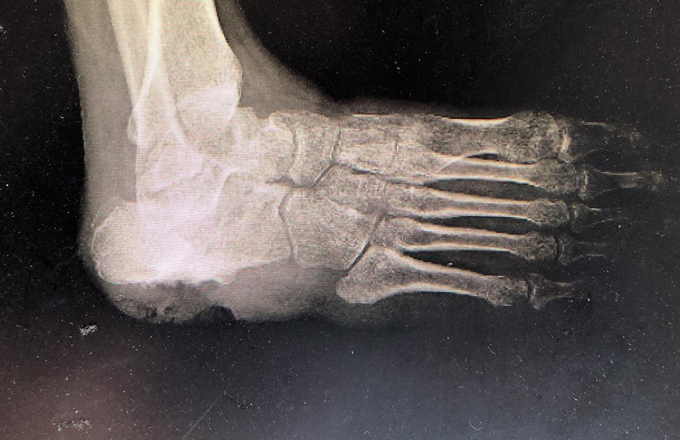

每天行走在刀尖上的“人鱼公主”,疼痛居然是因为脚上长出了一颗“心”!

本网讯(文化策划中心丁建萍/文)海的女儿人鱼公主为了和心爱的王子生活在一起,向巫婆讨了一锅汤,她喝了后就拥有了一条纤细笔直的腿,但是每走一步,都会像走在刀尖上一样,疼痛剧烈。 &emsp...2020-08-282002 -